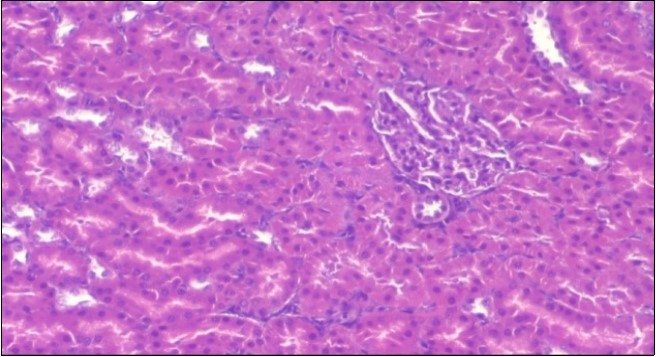

The histological examination of the kidney of the control rats fed on a standard diet showing normal rounded capsules with normal Bowman's glomeruli, round proximal tubules and elongated distal tubules with high cuboidal cells figure 1. The rats fed (HFD) showed fatty degeneration of the tubules with eosinophilic material deposition, glomerular atrophy with wide urinary space and distal tubules with extrusion of nuclei into lumen figure 2. By comparison kidneys of rats which were treated by fennel after being obese and the control rats observed partial improvement in both Bowman's capsules and proximal tubules. Note the distal tubules show less focal fatty infiltration figure 3.While examination of rats kidney that were treated by ator after obesity showed improvement in Bowman's capsules with normal glomerular and partial improvement in proximal tubules and distal tubules, figure 4. Kidney of rats that were treated by fennel and ator after obesity and the control rats showed high improvement in the tissues with normal glomerular and that Most of Bowman's capsules and renal tubules, restoring their normal appearance figure 5.

Figure 1.Photomicrogragh of kidney section of control rat showing normal rounded capsules with normal Bowman,s glomeruli, round proximal tubules and elongated distal tubules with high cuboidal cells , (H&E) (40X).